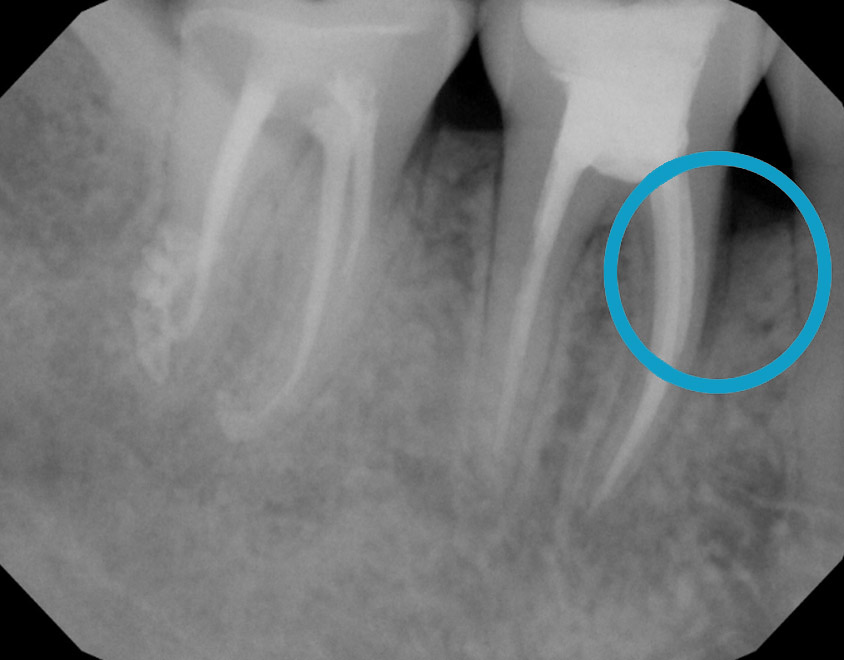

Treat severe gum disease and help the bone grow

One year after treatment, the bone has grown completely to a healthy level. It is all your own natural bone without the need for bone grafting.

Bone healing with ozone treatment and SRP

Reverse Gum Disease: Bone Healing